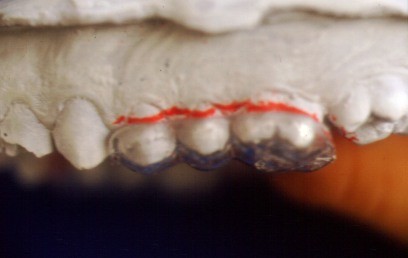

FIGURA 2.- Férula sobre

modelo.

Totalmente escotada por mesial y distal

Se recorta la plancha hacia

mesial desde primer premolar de un lado a primer premolar del cuadrante

opuesto. Distalmente liberaremos a partir de los primeros molares (figs.

2, 3).